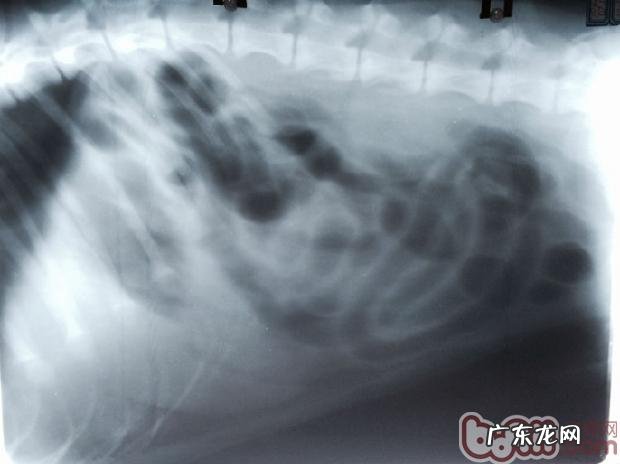

X光显示信息很多汽体填满肠胃内,猜疑有堵塞部位

提议在次开展钡餐造影,以明确堵塞部位及肠道详细情况 。一个小时后的影片,钡餐在肠胃内末见向后排尽,且已显著出現堵塞物影象